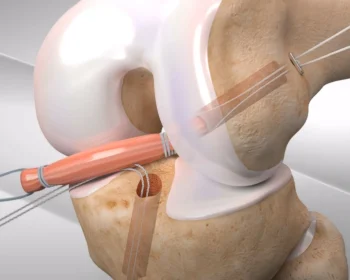

Ligamentous reconstruction around the knee is a surgical procedure that repairs or replaces torn ligaments, restoring stability and function to the joint.

ACL and PCL arthroscopic reconstruction is a minimally invasive surgery to repair torn ligaments in the knee, promoting faster recovery and improved stability.